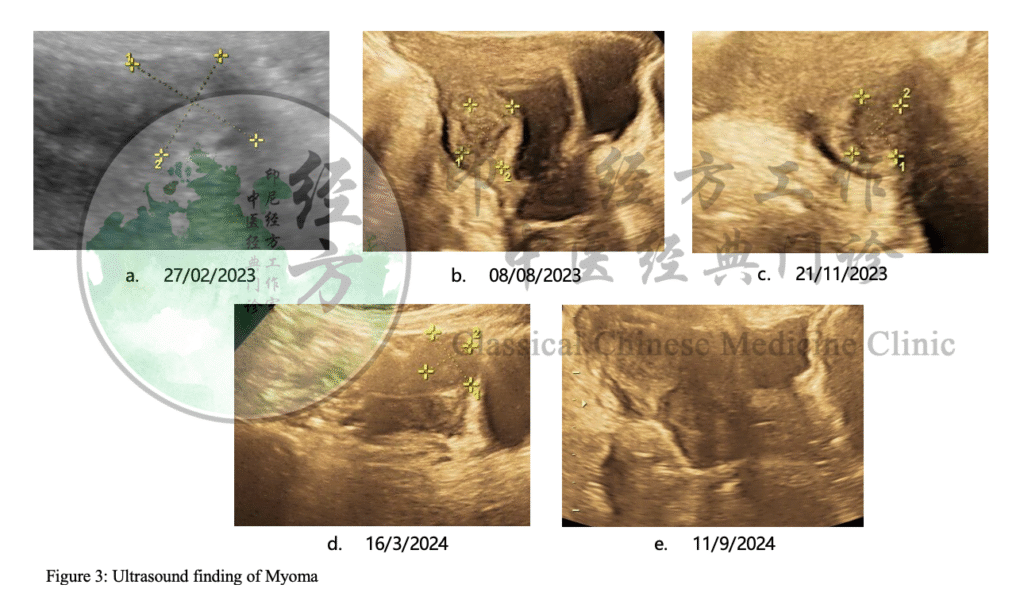

27 Februari 2023: Kista mengecil menjadi 4,55 × 3,83 cm, muncul mioma 2,62 × 2,10 cm.

8 Agustus 2023: Kista mengecil menjadi 1,62 × 1,75 cm, mioma 2,3 × 2,36 cm.

21 November 2023: Kista 2,32 × 1,71 cm, mioma 1,83 × 1,80 cm.

16 Maret 2024: Kista menghilang, mioma 2,34 × 1,84 cm.

11 September 2024: Kista dan mioma sama-sama hilang, tanpa kekambuhan.